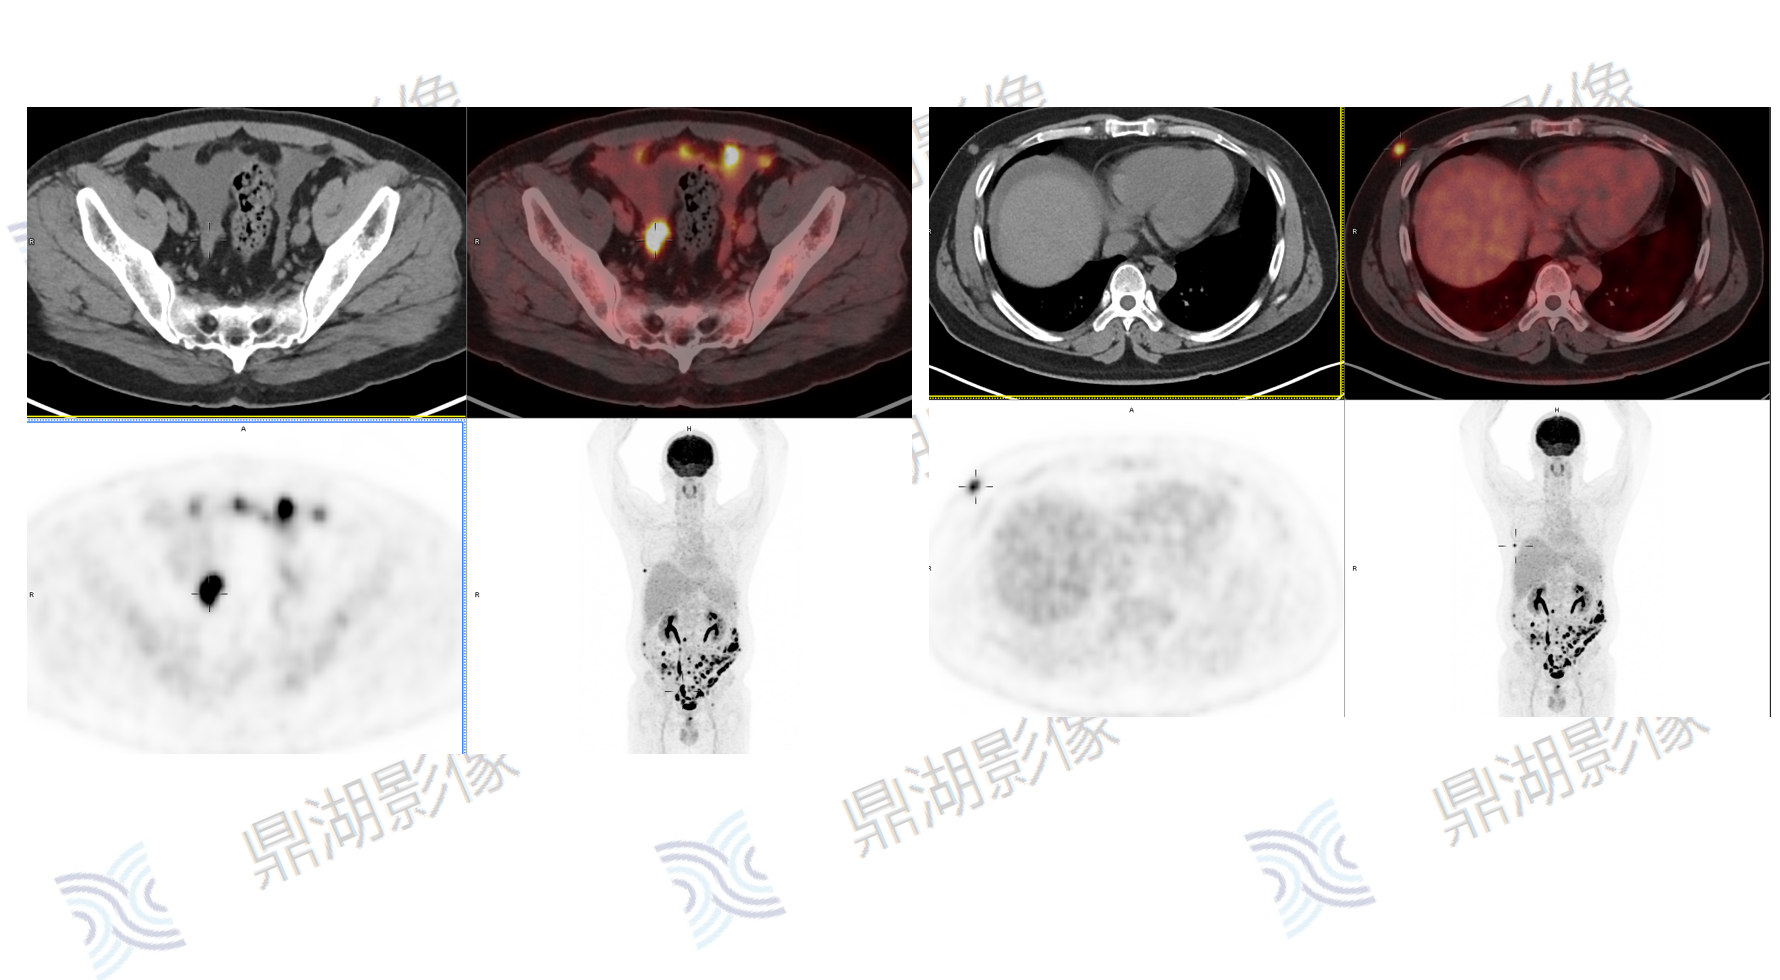

患者,女性,80岁

主诉:左侧肢体无力2周

现病史:患者两周前发现无明显诱因左侧肢体无力、行走不稳伴发热,表现为走路向左侧偏斜,无恶心呕吐,一直未予以治疗。

既往史:无高血压、糖尿病病史;无传染病病史

查体:无明显异常